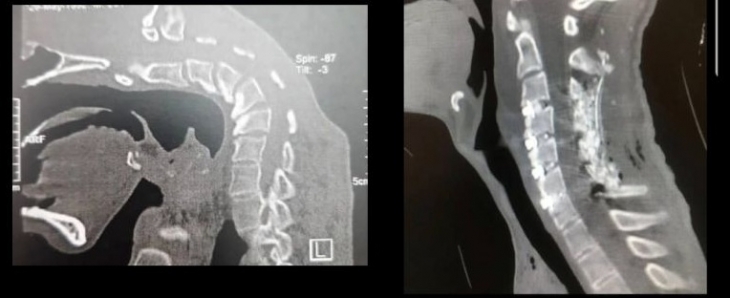

약물 중독으로 머리떨굼증후군(Dropped Head Syndrome, DHS)과 경추후만증(Cervical Kyphoscoliosis, CKS)을 얻은 20대 남성의 엑스레이 사진. 이란 이스파한의과대학 신경외과 자료

의료진은 정신과 치료와 함께 꺾인 목뼈를 바로 세우는 수술을 병행했다. 목뼈와 근육 일부를 제거하고, 나사와 막대 등으로 흐트러진 균형을 바로잡는 교정 방식을 활용했다.

수술은 성공적이었고 다음날부터 정상 보행한 환자는 3일 후 퇴원했다. 1년의 추적 관찰에서도 목뼈 정렬과 교정이 만족스럽게 개선된 것으로 확인됐다.